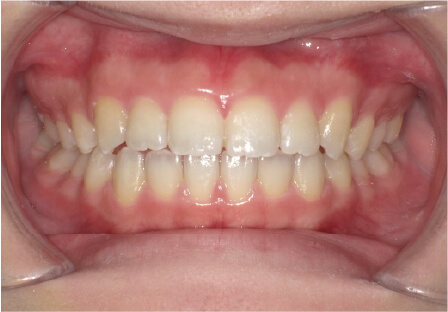

叢生の症例

11歳

/

女性

相談内容

上の前歯の歯並びが気になる(マイオスマイルからの移行)

カウンセリング・診断結果

インビザライン、拡大入れながらスペースを作成、下Eは出てきたら削りながら進める

治療内容・方法

全額アライナー矯正 クリアコレクト

術後の経過・現在の様子

クリアライナー使用

治療のリスク

痛み・歯根吸収・歯肉退縮・虫歯・後戻り

費用・治療期間

移行料金220,000円、月々16,500円、1年1ヶ月+myo2年3ヶ月

トレーニングなど